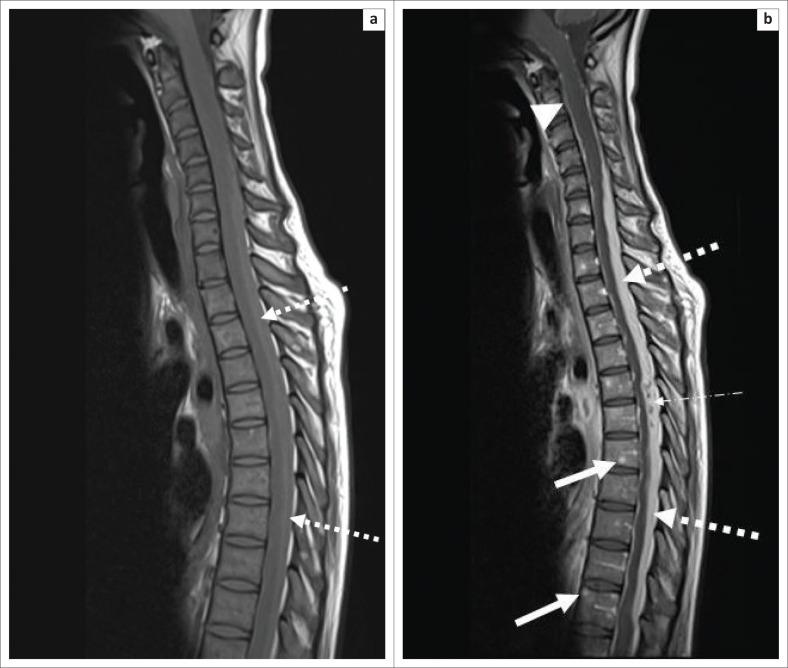

Extra-pulmonary tuberculosis (EPTB), caused by , is the leading cause of communicable disease-related deaths in people with human immunodeficiency virus (HIV) worldwide and in South Africa. disseminates haematogenously from an active primary lung focus and may affect extra-pulmonary sites in up to 15% of patients. Extra-pulmonary TB may present with a normal chest radiograph, which often causes a significant diagnostic dilemma. This review describes the main sites of involvement in EPTB, which is illustrated by local imaging examples.

由……引起的肺外结核病(EPTB)是全球和南非人类免疫缺陷病毒(HIV)感染者中与传染病相关死亡的主要原因。……从活跃的原发性肺部病灶经血行播散,高达15%的患者可能累及肺外部位。肺外结核病可能胸部X线片表现正常,这常常造成重大的诊断困境。本综述描述了肺外结核病的主要受累部位,并通过局部影像学实例进行说明。 (注:原文中“caused by ”和“disseminates haematogenously from an active primary lung focus and may affect extra-pulmonary sites in up to 15% of patients.”前缺失关键信息)